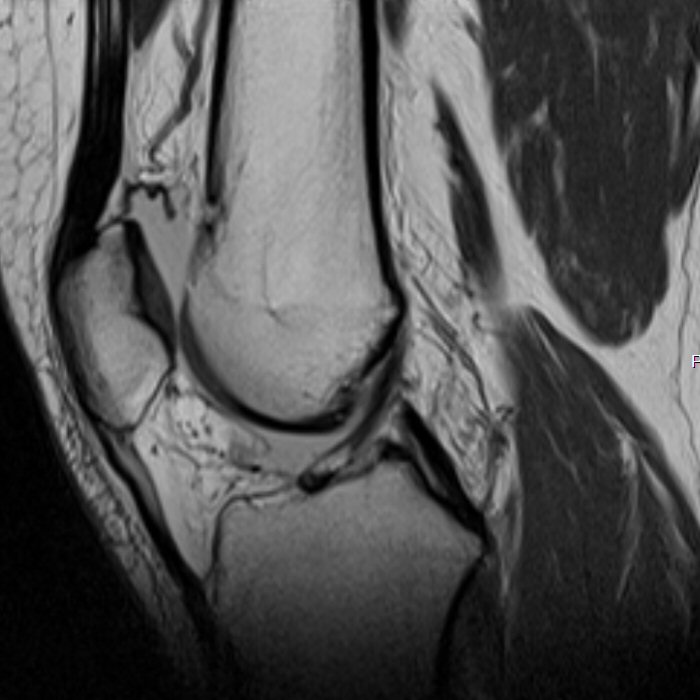

Det är bra att ha en rutin för hur man läser röntgenbilder generellt, även för MR-bilder. Ett exempel för knä kan vara så här:

Identifiera vilket som är lateralt (där man ser fibula). Börja laterala och gå mot medialt

Bläddra från ventralt till dorsalt, tillbaka till ventralt, upprepa vid behov.

Superiort till inferiort